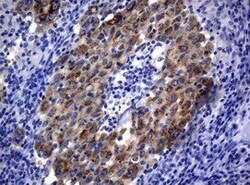

- Immunohistochemical staining of paraffin-embedded ALK-positive lung tumor xenograft using anti-ALK mouse monoclonal antibody. (TA801287, 1:50; heat-induced epitope retrieval by 1mM EDTA in 10mM Tris, pH8.0, 120°C for 3min)